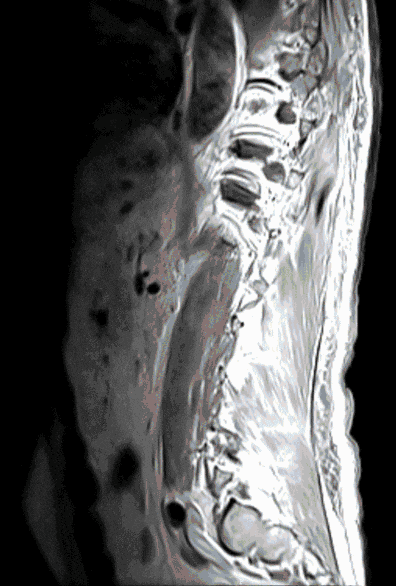

In approximately 5% of all cancer patients (e.g. patients with lung, prostate or breast cancer), the spine is affected by metastases. Metastases can endanger the stability of the spine or lead to pain and neurological dysfunction due to pressure on the spinal cord and nerves.